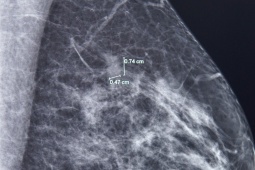

Bệnh nhân 61 tuổi chiến thắng ung thư vú nhờ phát hiện sớm

Ung thư vú đa ổ kích thước rất nhỏ (7mm và 3mm) được phát hiện trong lần tầm soát vú định kỳ. Với nhiều phụ nữ, đó có thể là tin dữ, nhưng với bà T.T.A (61 tuổi, TP.HCM), đây lại là “may mắn” vì bệnh ung thư vú của bà được phát hiện ở giai đoạn rất sớm, giúp hành trình điều trị sau đó nhanh chóng và hiệu quả.